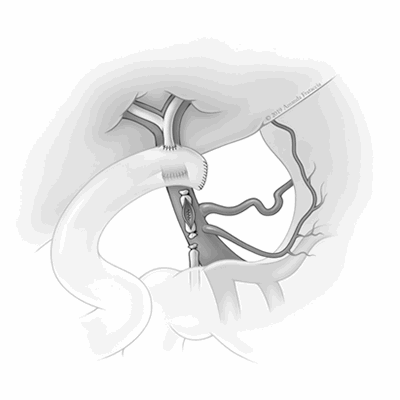

During this admission, a second episode of severe gastrointestinal bleeding urgently managed with esophagogastroduodenoscopy demonstrated bleeding from the major duodenal ampulla. ERCP demonstrated the opacification of the main portal vein located 3 cm to 4 cm from the ampulla (Figure 1A and Figure 1B), confirming the diagnosis of a PBF. The bleeding was controlled with a 15 mm extraction balloon, followed by the placement of a 10 mm x 8 cm fully covered Viabil® metal stent into the common bile duct. Stenting across the fistula allowed for tamponade of the fistulous defect and temporarily controlled bleeding. The patient underwent orthotopic liver transplantation with a cadaveric liver four days later.

Figure 1. ERCP cholangiogram; arrow points to site of porto-biliary fistulous tract